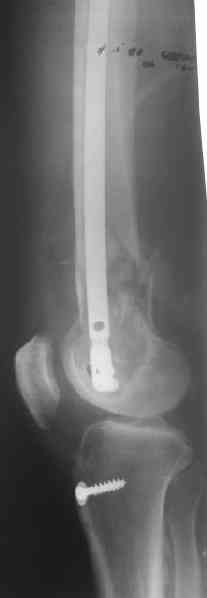

> Хотелось бы узнать какую тактику  лечения Вы предпочли? Речь идет о

> пациенте 60-ти лет с переломом  дистального отдела бедренной кости,

> фиксированного пластиной?

> Есть подозрение, что мыщелки отрепонированы между собой неидеально,

> как-будто наружный завален кзади (угол открыт кпереди). Надо удалять все

> железо, репонировать открыто суставные поверхности и...

Это предложение показалось слишком радикальным. Неровно оно совсем

чуть, по межмыщелковой борозде, т.е. в ненагружемой зоне, да уже и

срослось хотя бы там... И не 18 лет пациенту.

Удалили ластину без проблем. Выявилась значительная подвижность. В

винт. И сделали антгерадное штифтование, как говорится, "по принятой в

клинике методике".

Длину восстановили, возможно, даже с изьбытком, ну да динамизируем

пораньше. Введенные в овальное отверстие  дистальые винты имеют

угловую стабильность.  Снимки приложены. Заранее спасибо за критику и

комментарии.